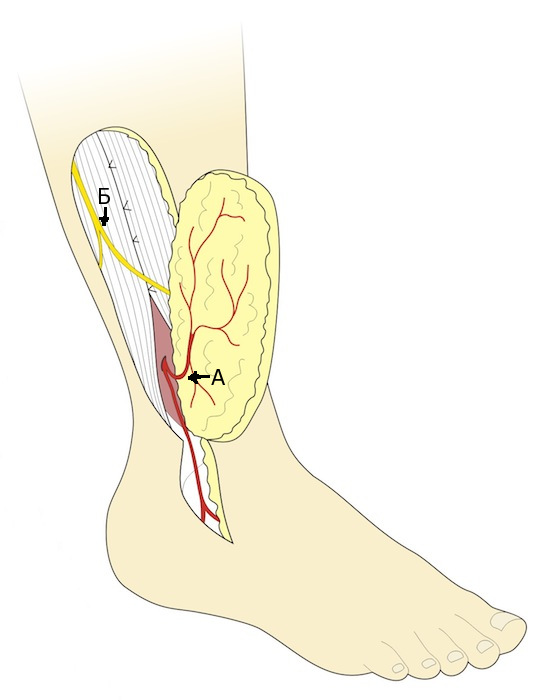

Ротированный лоскут

Кровоснабжение обеспечивается перфорирующей ветвью малоберцовой артерии, которая отдает кожную ветвь лоскуту. В этом типе лоскута сосудистая ножка имеет антеградный кровоток от перфорантной ветви малоберцовой артерии. Лоскут может быть ротирован в качестве островкового или пропеллер лоскута для закрытия дефекта мягких тканей нижней трети голени и передней поверхности голеностопного сустава (рис. 5) [5].

Рис. 5. Ротированный лоскут. Этот тип лоскута кровоснабжается антеградным кровотоком от перфорантной ветви малоберцовой артерии. В рассечение кожи над латеральной лодыжкой нет необходимости, если точкой ротации (pivot point) лоскута является перфорантная артерия (А- кожная ветвь в лоскуте; Б – поверхностный малоберцовый нерв).